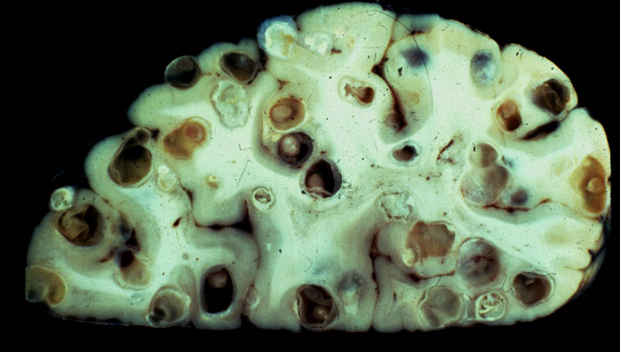

Проникая в мозг, гельминт заселяется в тех областях, где он может свободно перемещаться (основание мозга, оболочка, желудочки). Когда попадает туда, личинка превращается в цистицерк. Цистицерк представляет собой пузырь, наполненный прозрачной жидкостью, диаметр которого колеблется от 3 до 15 мм.

Внутри пузыря расположена головка финна (сколекс с присосками и крючками). Этот процесс позволяет личинке сохранять способность к жизни до 25 лет. Гибель паразита приводит к образованию кальцификатов вокруг цистицерка.

С использованием магнитно-резонансной томографии можно обнаружить очаги инфекции. Они представляют собой кластеры винограда или отдельные шарообразные образования. Цистицерки хорошо видны на снимках МРТ. С большой точностью определяется их местоположение и уровень вызванных ими воспалительных процессов в оболочках мозга.